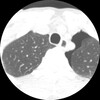

How does Interstitial Pneumonia appear radiographically?

-“Honeycomb Lung” as seen on CT -Interstitial tissue thicker between all of the alveoli (inflammation between the air spaces) -Tissue between alveoli more visible ## Footnote No heavy mucus, bronchiectasis as seen in CF

What pathology is seen here?

Interstitial Pneumonia

52